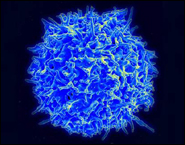

Ученые и врачи с помощью новой технологии вылечили от рака смертельно больного человека. Новая методика может стать мощным лекарством для лечения онкологических и многих других заболеваний.

Онкологические заболевания, к сожалению, очень распространены и к тому же стоят на пути к радикальному продлению жизни. Современные средства лечения рака не очень надежны, но ученые, возможно, нашли эффективное средство лечения всех видов рака, а также множества других заболеваний. Суть новой технологии заключается в «обучении» иммунных клеток пациента борьбе с клетками рака. Первые успешные опыты по лечению пациентов в тяжелом состоянии продемонстрировали высочайшую эффективность новой методики.

Нику Уилкинсу был поставлен диагноз лейкемия, когда ему было всего 4 года. К сожалению, ни химиотерапия, ни пересадка костного мозга от его сестры не помогли избавиться от болезни. К 14 годам стало ясно, что все существующие способы лечения не помогают, а значит Ник скорее всего умрет. К счастью, мальчика включили в экспериментальную программу лечения, разработанную в Университете Пенсильвании. Вместе с 20-ю другими молодыми пациентами Ник Уилкинс прошел курс экспериментального лечения в Детской больнице Филадельфии. На этих выходных на ежегодном собрании Американского гематологического общества врачи представили доклад об успешном завершении эксперимента. Удивительно, но уже через 2 месяца после лечения Ник полностью избавился от рака. Из 21 пациента у 18 наблюдалось полное излечение всего лишь после одного курса лечения.

Новая терапия основана на использовании Т-клеток иммунной системы пациента и, при должной квалификации врачей, потенциально может быть осуществлена в любом современном медицинском центре. Лечение проходит следующим образом: сначала врачи берут у пациента иммунные Т-клетки и перепрограммируют их путем передачи в новых генов. Модифицированные клетки «нацеливают» на определенные раковые клетки, и таким образом Т-клетки пациента приобретают свойство обнаруживать и атаковать опухолевые клетки. После перепрограммирования, Т-клетки вводят в тело пациента, у которого ранее эти самые клетки были взяты. В теле человека каждая перепрограммированная клетка передает свою новую генетическую модификацию 10 000 других клеток. Таким образом, в организме пациента появляется большое количество «охотников», которые начинают уничтожать раковые клетки. По сути, ученые «обучили» иммунитет бороться с раком точно так же, как он борется, например, с простудой.

У лечения есть свои особенности, так, после введения модифицированных клеток началась активная борьба с раком, которая вылилась в обычные симптомы борьбы с инфекцией: высокая температура, слабость и т.п. В это время пациентов держали в отделении интенсивной терапии, например Ник Уилкинс провел там день. Однако побочные эффекты нового лечения не идут ни в какое сравнение с тяжелейшим отравлением организма в результате противораковой химиотерапии или опасностями и болезненностью операции по пересадке костного мозга.

Новая технология лечения позволяет «научить» иммунные Т-клетки атаковать клетки опухоли. Подобная методика, теоретически, может применяться для лечения любых видов рака на любой стадии, а также многих инфекционных заболеваний и тяжелых отравлений

Новая методика очень эффективна. У Ника спустя 2 месяца после лечения в крови не обнаружено ни одной раковой клетки. Более того, генетически модифицированные Т-клетки выжили и могут существовать в крови пациентов в течение минимум 3 лет. Это значит, что пациенты надежно защищены от рецидива болезни собственной иммунной системой.

Врачи смотрят на новую технологию оптимистично. Клинические эксперименты с ней ведутся лишь с 2010 года, но до сих пор количество рецидивов остается очень низким, в том числе и у взрослых пациентов. Так, из 12 полностью излеченных взрослых, только у одного наблюдался рецидив, причем рецидивы после терапии модифицированными Т-клетками поддаются лечению намного легче.

Сегодня новая методика лечения доступна лишь в ходе экспериментальных клинических программ, но врачи полагают, что через 3-5 лет она станет обычной клинической практикой.

«Пятнадцать лет назад я был в лаборатории и смотрел, как модифицированные Т-клетки убивают раковые в чашке Петри. Затем были эксперименты на мышах и, наконец, лечение людей, – рассказывает доктор Ренье Брентьен (Renier Brentjens). - Я никогда не забуду первого пациента, у которого в костном мозге было огромное количество раковых клеток. Но после новой терапии, я посмотрел в микроскоп и не смог найти ни одной раковой клетки. Это просто фантастика».